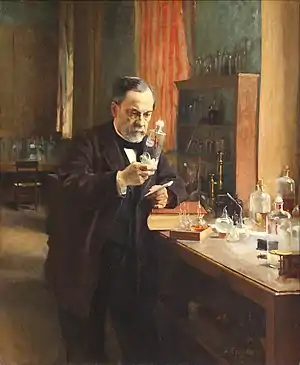

Medicine has been practiced since prehistoric times, and for most of this time it was an art (an area of creativity and skill), frequently having connections to the religious and philosophical beliefs of local culture. For example, a medicine man would apply herbs and say prayers for healing, or an ancient philosopher and physician would apply bloodletting according to the theories of humorism. In recent centuries, since the advent of modern science, most medicine has become a combination of art and science (both basic and applied, under the umbrella of medical science). For example, while stitching technique for sutures is an art learned through practice, knowledge of what happens at the cellular and molecular level in the tissues being stitched arises through science.

Prescientific forms of medicine, now known as traditional medicine or folk medicine, remain commonly used in the absence of scientific medicine and are thus called alternative medicine. Alternative treatments outside of scientific medicine with ethical, safety and efficacy concerns are termed quackery. (Full article...)